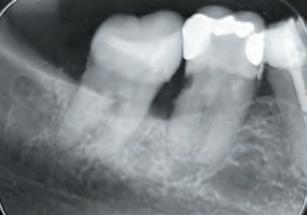

A 77-year-old Caucasian patient presented to the dental clinic after five years without dental care. The clinical findings showed significant bone loss, chronic periodontitis, and loss of some teeth that stabilized the occlusion. The patient reported cold sensitivity in tooth #46, especially when ingesting liquids.

Periapical X-ray confirmed the findings of the clinical examination and root caries was also detected in the distal root of tooth #46, which answered positively to the sensitivity test (Fig.1-2).

The treatment plan began with a focus on returning the patient to adequate periodontal health. In a subsequent session, with improved condition of the periodontium, the restoration of tooth #46 was performed. Under block anesthesia of right inferior alveolar nerve and rubber dam isolation, the amalgam restoration was completely removed and access to the caries cavity obtained (Fig. 3-5). Despite the proximity to the pulp tissue, no exposure occurred, and the class II cavity was fully restored with Biodentine™ (Fig. 6-8).